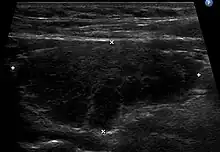

L'échographie de la thyroïde montre un goitre hypoéchogène[20],[18]. Le parenchyme thyroïdien devient plus hétérogène au cours de l'évolution. On peut notamment mettre en évidence des pseudo-nodules et des nodules de régénérations hyperéchogènes (white knight)[18]. Des ganglions récurrentiels peuvent être visualisés[18]. La vascularisation est hétérogène en Doppler couleur. L'étude en Doppler pulsé retrouve une élévation des vitesses systoliques[18], toutefois moindre que dans la maladie de Basedow.